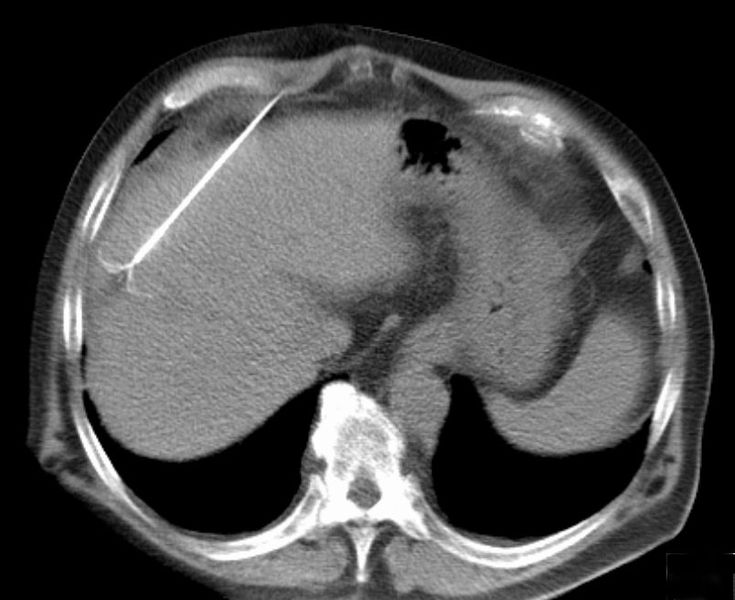

Radiofrequency ablation (RFA) is a minimally invasive treatment, one of several types of ablation therapy, where surgery is not a good option. Guided by imaging, a thin needle or probe is inserted through the skin and into the tumor.The probe passes alternating electrical current (radiofrequency energy) through the tumor tissue generating heat at the site of the tumor. This causes tumor necrosis (cell death) and destruction of cancerous tissue.The dead cells eventually turn into a harmless scar.

| CT scan showing radiofrequency ablation of a liver lesion |

RFA is used to treat numerous tumors including those in the liver, bone, kidney, and lung. A key advantage is it selectively destroys cancer cells while leaving healthy cells unaffected. The size and location of tumors are a factor in whether RFA can be used.